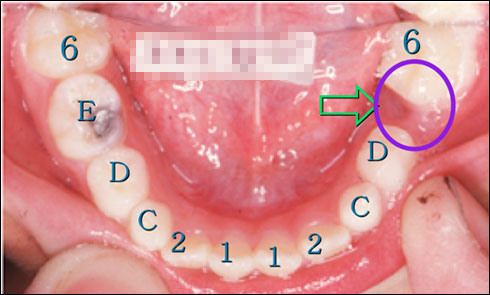

乳臼歯の骨性癒着による咬合異常

2. 歯年齢 III A 期

4. 下顎左側第一大臼歯の著しい近心傾斜

5. 下顎左側第二乳臼歯の埋伏低位と後継永久歯胚の位置異常

1. 歯列周長の再獲得のために下顎第一大臼歯 の直立

2. 低位乳臼歯の自然萌出なければ下顎第二乳臼歯の抜歯

3. 下顎第二小臼歯の歯列内への萌出誘導

リンガルアーチ(SLA)装置による、下顎左側第一大臼歯の整直(直立)

初診時III A期

III C期